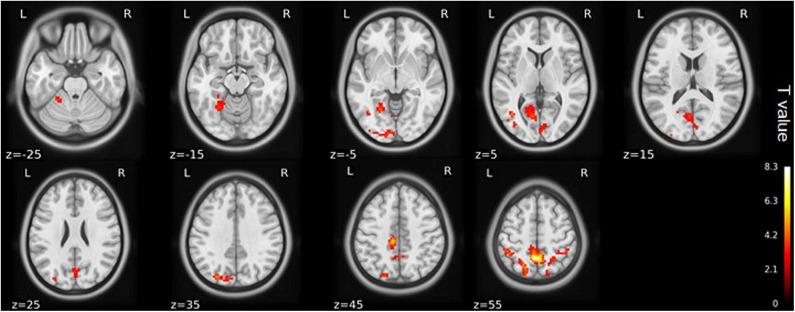

This study aimed to investigate the brain functional alterations with resting-state functional magnetic resonance imaging (rs-fMRI) in older patients with knee osteoarthritis (KOA) before and after total knee arthroplasty (TKA) and to assess the causal relationship of the brain function and neuropsychological changes. We performed rs-fMRI to investigate brain function of 23 patients aged ≥65 with KOA and 23 healthy matched controls. Of the KOA patients, 15 completed postoperative rs-fMRI examinations. Analyzes of the amplitude of low-frequency fluctuation (ALFF) and functional connectivity (FC) were used to estimate differences in brain functional parameters between KOA patients, postoperative patients, and the controls. The relationship between changes of pre- and post-surgical status in ALFF and neuropsychological test results was analyzed. Compared with the controls, all patients with KOA exhibited decreased ALFF in the default mode network (bilateral angular gyrus, precuneus gyrus, medial superior frontal gyrus) and increased ALFF in the bilateral amygdala and cerebellum posterior lobe before surgery ( < 0.001). Altered ALFF persisted in the same brain regions 1 week postoperatively. The decreased ALFF in the left precuneus gyrus and middle temporal gyrus was found after surgery when compared with preoperative data ( < 0.01). Preoperatively, the KOA patients exhibited increased FC between the left precuneus gyrus and the right supplementary motor area compared to the controls ( < 0.001), but this connectivity became no significant difference after TKA. The left Cerebelum_9 was found to have decreased FC with the right precuneus gyrus postoperatively ( < 0.001) although this was not significantly different before surgery. The significantly altered ALFF values were not correlated with changes in cognitive assessment scores. In older patients with end-stage KOA, functional alterations in important brain regions were detected with the persistence and further changes observed at an early stage after knee replacement. Our data further our understanding of brain functional abnormalities and cognitive impairment in older patients following knee replacement, which may provide therapeutic targets for preventive/treatment strategy to be developed. Clinical Trial Registration: http://www.chictr.org.cn/index.aspx, ChiCTR1800016437; Registered June 1, 2018.

本研究旨在通过静息态功能磁共振成像(rs-fMRI)调查老年膝骨关节炎(KOA)患者全膝关节置换术(TKA)前后的脑功能改变,并评估脑功能与神经心理变化之间的因果关系。我们对23例年龄≥65岁的KOA患者及23名匹配的健康对照者进行rs-fMRI以研究脑功能。其中15例KOA患者完成了术后rs-fMRI检查。采用低频振幅(ALFF)分析和功能连接(FC)分析来评估KOA患者、术后患者及对照者之间脑功能参数的差异。分析了手术前后ALFF变化与神经心理测试结果之间的关系。与对照组相比,所有KOA患者术前默认模式网络(双侧角回、楔前回、额上回中部)的ALFF均降低,双侧杏仁核和小脑后叶的ALFF增加(<0.001)。术后1周,相同脑区的ALFF改变持续存在。与术前数据相比,术后发现左侧楔前回和颞中回的ALFF降低(<0.01)。术前,与对照组相比,KOA患者左侧楔前回与右侧辅助运动区之间的FC增加(<0.001),但TKA术后这种连接性无显著差异。术后发现左侧小脑_9与右侧楔前回的FC降低(<0.001),尽管术前无显著差异。ALFF值的显著改变与认知评估评分的变化无关。在老年终末期KOA患者中,检测到重要脑区的功能改变,且在膝关节置换术后早期观察到这些改变持续存在并进一步变化。我们的数据进一步加深了我们对老年患者膝关节置换后脑功能异常和认知障碍的理解可能为制定预防/治疗策略提供治疗靶点。临床试验注册:http://www.chictr.org.cn/index.aspx,ChiCTR1800016437;2018年6月1日注册。